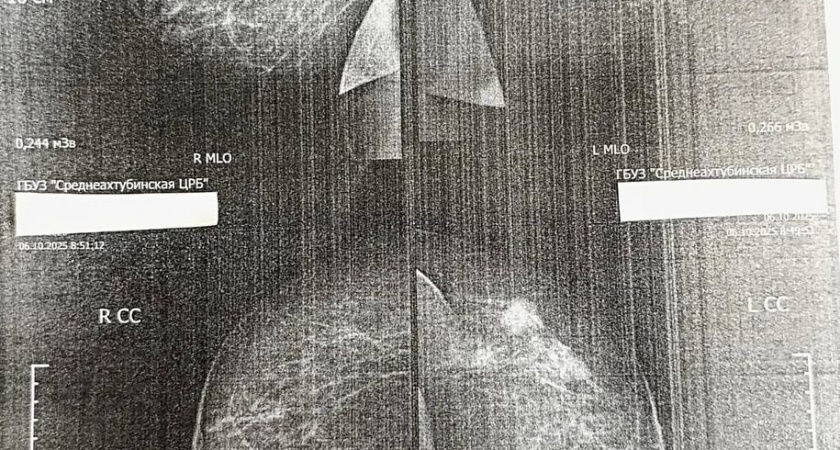

Во время того же осмотра при маммографии врачи обнаружили опухоль в молочной железе. Пациентку направили в Волгоградский областной онкологический диспансер, где диагноз подтвердился. Сейчас она проходит предоперационное лечение в специализированном медицинском центре.